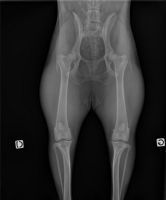

Dépistage officiel de la dysplasie de la hanche et du coude.